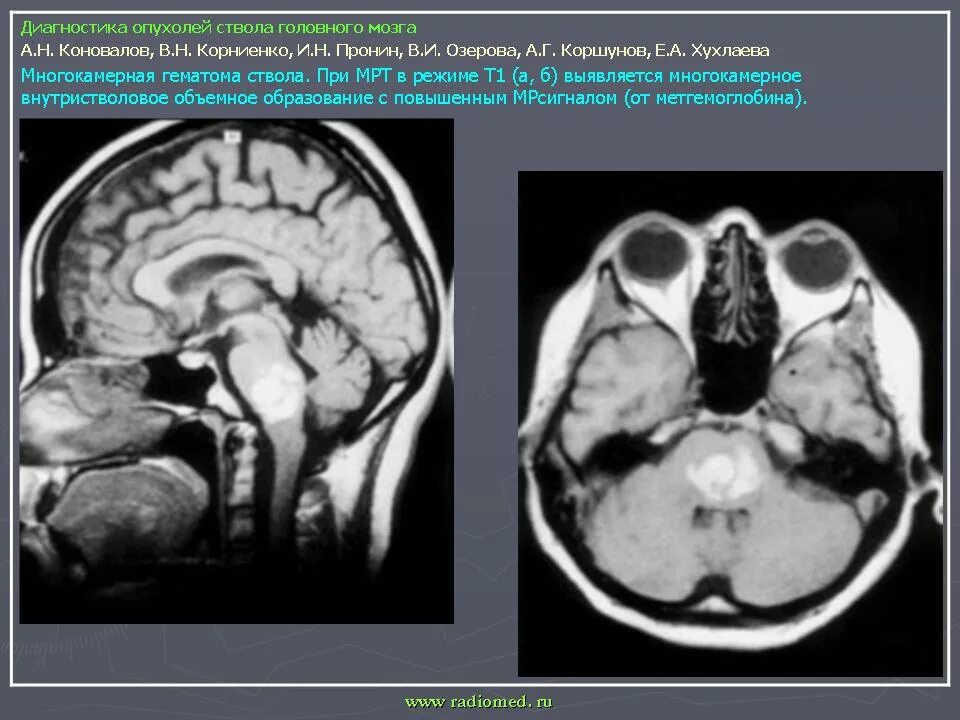

Сколько живут с доброкачественной опухолью головного мозга